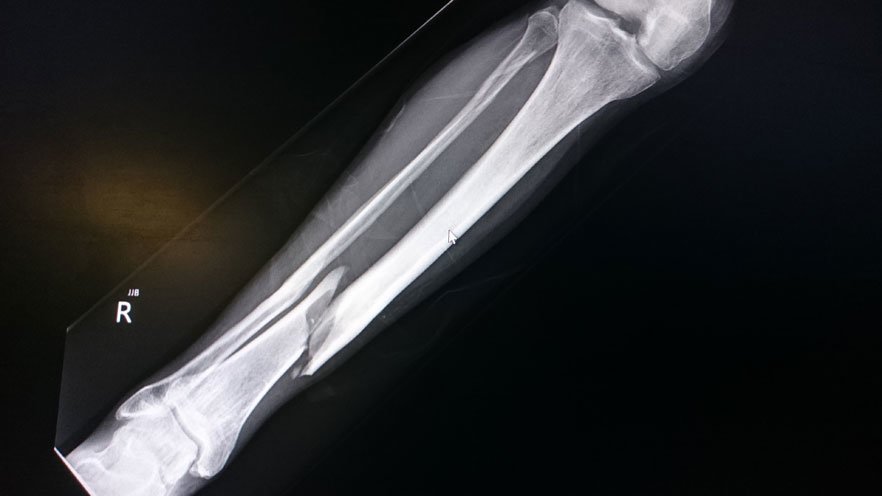

Bones are the hardest, sturdiest parts of our bodies. But trauma — such as from a fall, car accident, or sports injury — can break or dislocate even the strongest bones.

X-ray of a broken bone